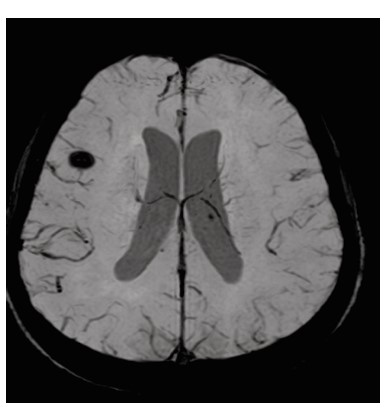

Dengue fever, a mosquito borne viral illness, is endemic in many parts of the world, particularly in tropical and subtropical regions. It is caused by four distinct serotypes (DENV 1–4) of single stranded RNA viruses from the Flaviviridae family. Although it is generally considered non-neurotropic, certain strains, especially DENV-2 and DENV-3, have been associated with neurological involvement. Neurological complications can include encephalopathy, encephalitis, meningitis, acute disseminated encephalomyelitis (ADEM), stroke, and Guillain-Barré syndrome. Dengue encephalitis, a relatively uncommon but serious manifestation, arises from direct viral invasion of neural tissue. This case report presents a patient with altered mental status and characteristic MRI findings symmetrical involvement of the thalami and cerebellum, known as the “double doughnut sign” indicative of dengue encephalitis. Cerebrospinal fluid analysis confirmed the diagnosis. Early recognition, neuroimaging, and supportive management with immunomodulation played a crucial role in the patient’s recovery. Clinicians should maintain a high index of suspicion for dengue encephalitis in endemic areas when encountering unexplained encephalopathy.